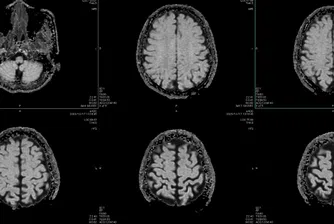

Учени идентифицират пет „епохи“ в развитието на човешкия мозък

Проучването, базирано на мозъчни сканирания на близо 4 000 души на възраст от под една година до 90, картографира невралните връзки и тяхната еволюция през живота ни